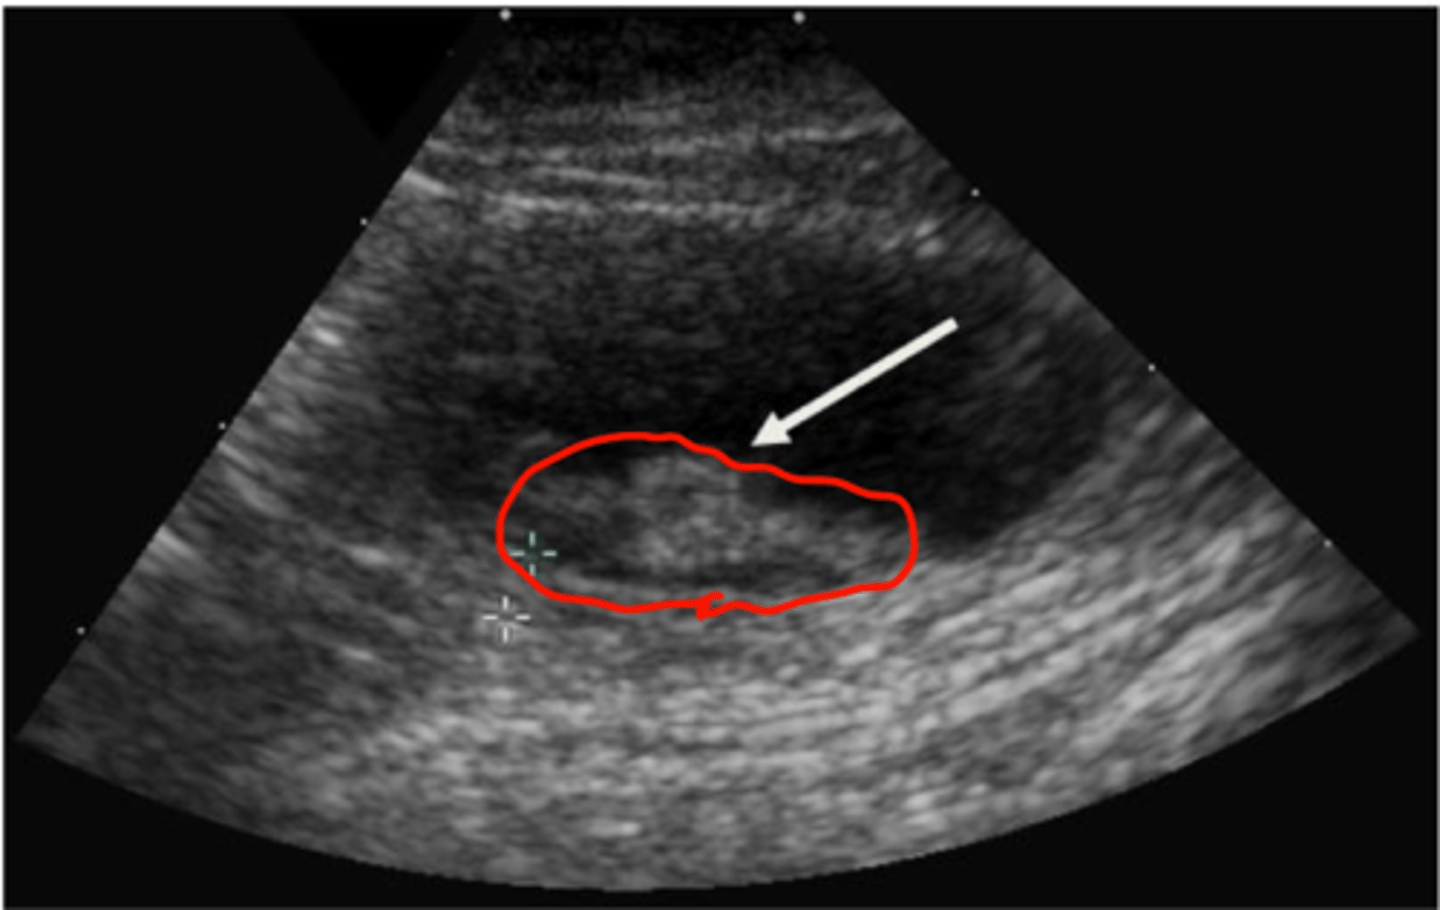

What are some abnormal findings on ultrasonography that would indicate urinary bladder calculi?

Abnormal echogenicity (normal urine is anechoic)

hyperechoic shadow interface

Thickened bladder wall

What are some characteristics of bladder neoplasia on ultrasound?

Heterogenous mass

Often located at trigone/prostate/urethra in dogs

May be at trigone or other bladder regions in cats

Important to check medial iliac lymph nodes

Check ventral aspect of lumbar vertebra on radiograph for metastasis to bone

transitional cell carcinoma is most common